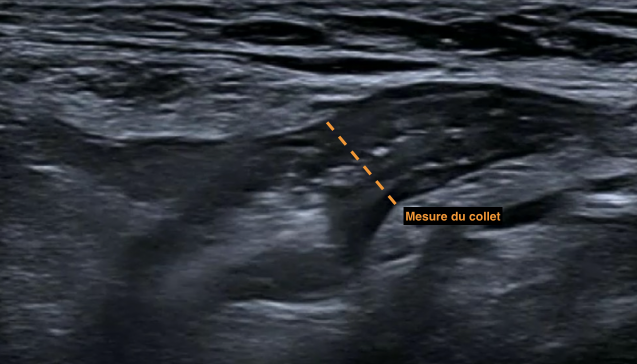

Coupe sagittale

- Confirme l’hernie

- Mesure le collet